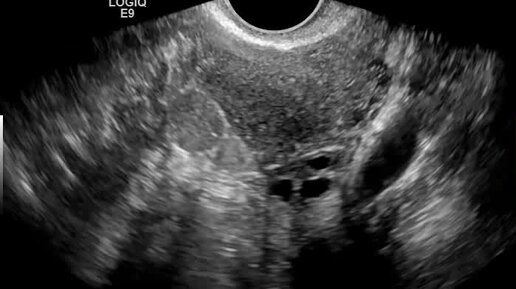

Видео: Поперечное сканирование матки. Яичник расположен по задней поверхности матки. Спаечный процесс